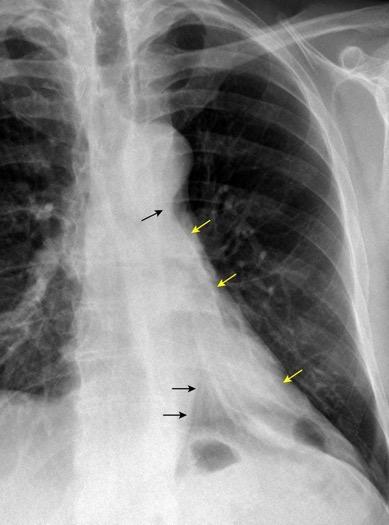

Ganglios retroperitoneales (flechas negras)

germinales del testículo izquierdo Nódulos pulmonares múltiples. (flechas verdes). Ganglios paratraqueales. (flechas amarillas). Dudoso ensanchamiento retrocrural (flechas negras)

Panda A et al. “Straddling Across Boundaries”. Thoracoabdominal Lesions: Spectrum and Pattern Approach. Curr Probl Diagn Radiol, 2015